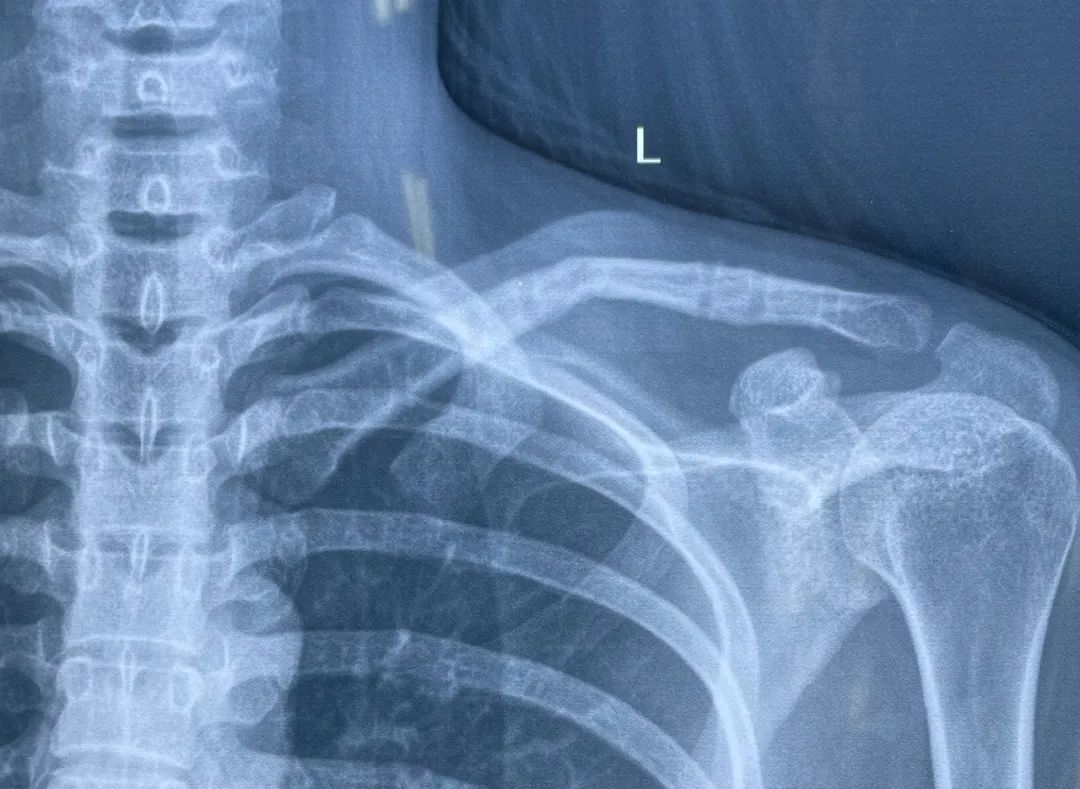

给予内固定取出术,术后复查 X 线:

术后复查锁骨对位对线良好。

本病例内固定取出术前 X 线片未发现明显的骨折线,但内固定物取出后因缺乏钢板的支撑,在无明显受伤机制的情况下发生再骨折,这可能说明骨折并未完全愈合。

在缺乏 CT 进一步诊断的前提下, 仅凭借 X 线片报告的骨折愈合诊断结果并不能完全排除骨折未愈合!!